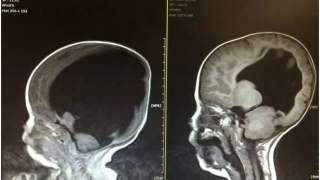

Lekarze namawiali parę na aborcję. Wiemy jak dziś rozwija się dziecko, które przyszło na świat bez mózgu

Aborcja miała być jedynym rozwiązaniem dla rodziny nienarodzonego chłopca. Lekarze namawiali parę na zabieg. Mimo to rodzice dziecka nie zgodzili się i...